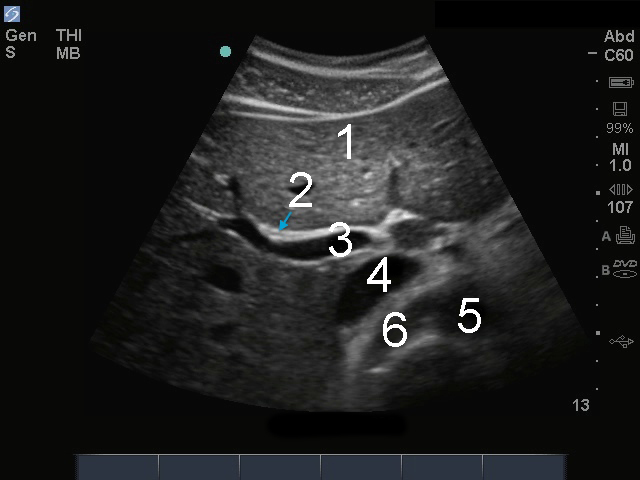

胆嚢総胆管(CBD)画像

門脈、CBD

肝臓

総胆管(CBD)

門脈 (PV)

下大静脈(IVC)

大動脈

右腎動脈 (RRA)